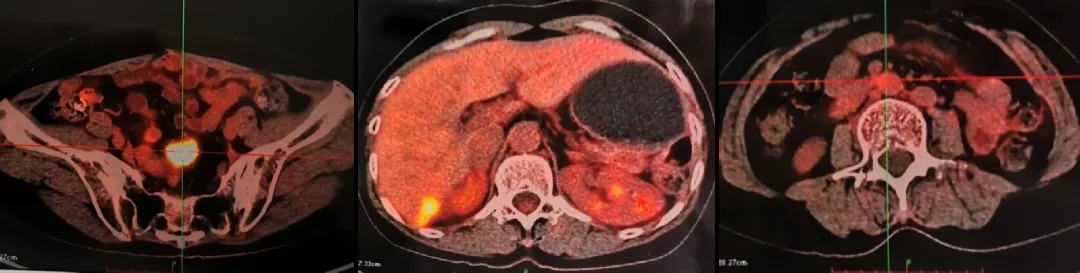

2013.5.10 PET-CT:肝肾隐窝、脾肾间隙、脾门旁、腹膜后可见斑片状、囊实性及结节状影,实质部分FDG代谢增高,考虑转移。

2013.5.10 PET-CT检查结果